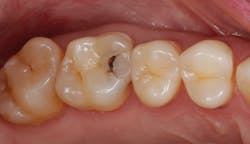

Let’s stop trying to “beat the blood”

After removing a two-week-old provisional, it’s a rare day that we don’t experience some minor inflammation of the soft tissues. Even with the best prototypes/provisionals and meticulous oral hygiene, gingival tissues will bleed, exude fluids, and generally cause problems when isolating teeth for adhesive delivery. With a direct composite, the existing decay is an irritant, and the best isolation device will not address the bleeding tissue adjacent to an extensive class II cavity.

With an inverted rubber dam, however, bleeding becomes a nonissue and allows the clinician to focus on preparation design, pulpal protection, adhesive strategies, and restoration placement—all in a clean and well-sealed environment.3 “Beating the blood” need not be your approach when one of dentistry’s least-used gems is close at hand (figures 6 and 7).